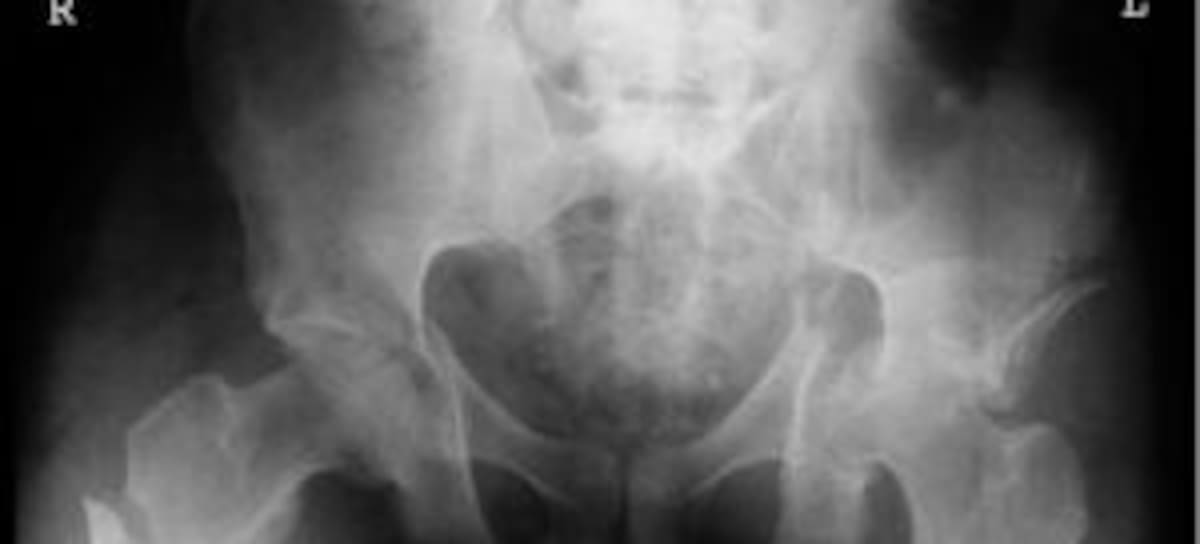

Se llama Sebastián y es un chico chileno de 23 años al que todos conocen ya como el 'joven del milagro'. No es para menos: Cayó desde una altura de 17 pisos y sólo sufrió una fractura de pelvis y otra de fémur

Las cámaras de seguridad grabaron el brutal impacto de Sebastián contra el techo de un parking y contra un coche. "Cuando iba cayendo soñaba que levitaba. Sentí el golpe pero no desperté, desperté en el hospital", cuenta el joven. Un caída desde 40 metros que inexplicablemente sólo le dejó una fractura de pelvis y de fémur.